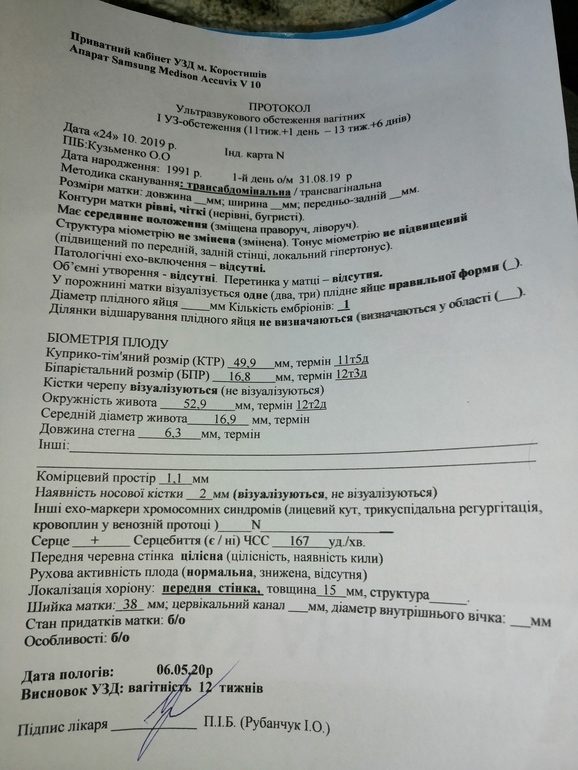

я говорю, что мне и так всё видно, зачем так тыкать, ответ был "для фотки". Думаю ну больная на голову," изнасиловала" датчиком)) ради фотки, матка начала болеть и поясница, в итоге из всего осмотра вымеряла ктр и твп и еще нашля омниотический тяж.

и еще нашля омниотический тяж.

Узи с жк